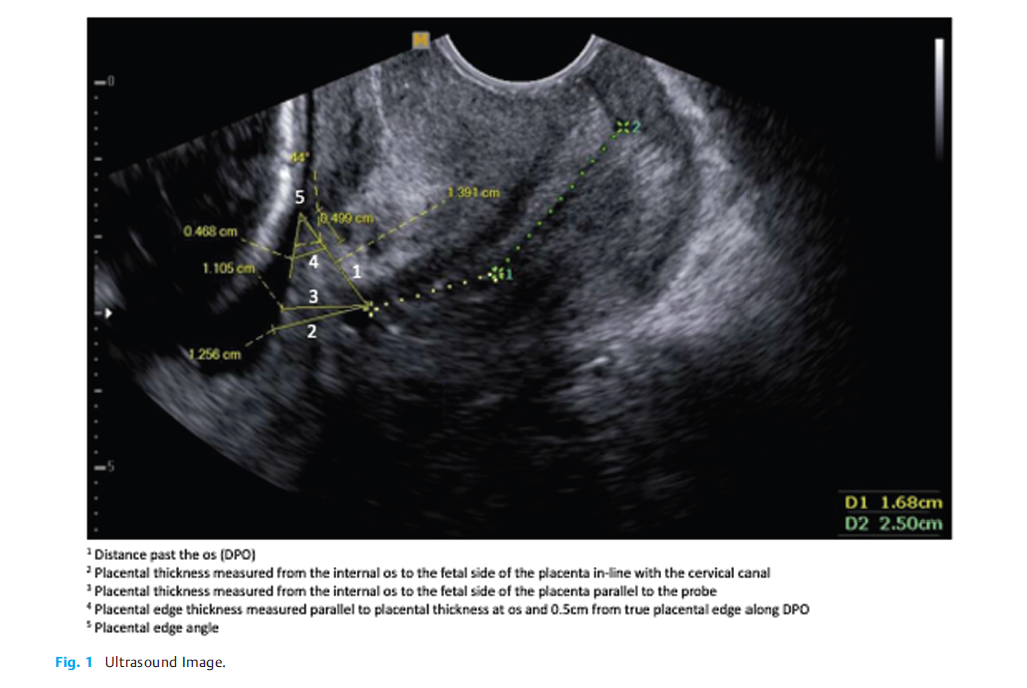

超声特征,见下图: